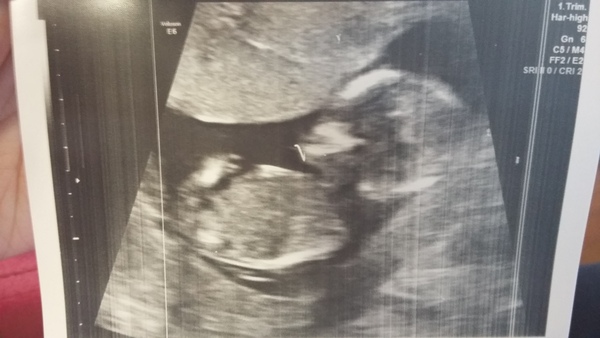

Lou we're having a private gender scan on Mother's Day and taking DS with us, so excited!

Doppler arrived yesterday and after lots of tries and youtube videos, finally found baby's heartbeat which was lovely. It was very quiet and the doppler couldn't pick it up to count it, but was definitely baby